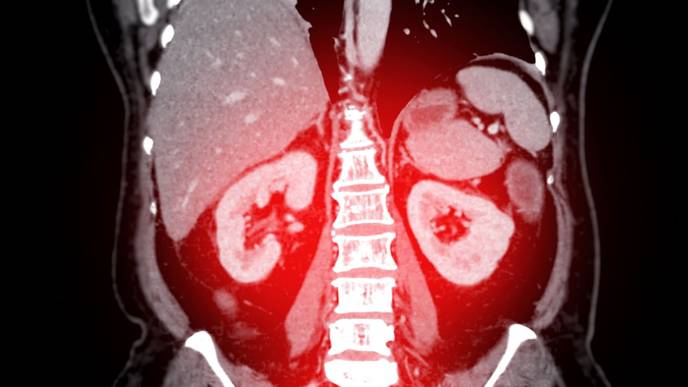

Urolithiasis Directly Linked to Osteoporosis, Finds Study

Researchers have found that urolithiasis, commonly known as kidney stones, has a direct causal relationship with osteoporosis (OP), independent of environmental factors. A recent study was published in The Journal of Clinical Endocrinology and Metabolism by Zijie Z. and colleagues. This study utilized Mendelian randomization (MR) and other genetic analyses to uncover the biological mechanisms linking these two conditions, emphasizing the importance of regular OP screening for patients with urolithiasis.

Although there has been an established association between urolithiasis and osteoporosis, its mechanisms are not very clear. Most of the studies focused on environmental factors, like diet. The question this study asks is whether urolithiasis itself can induce OP. The researchers use the data from the Japan BioBank to comprehensively assess and find possible direct links.